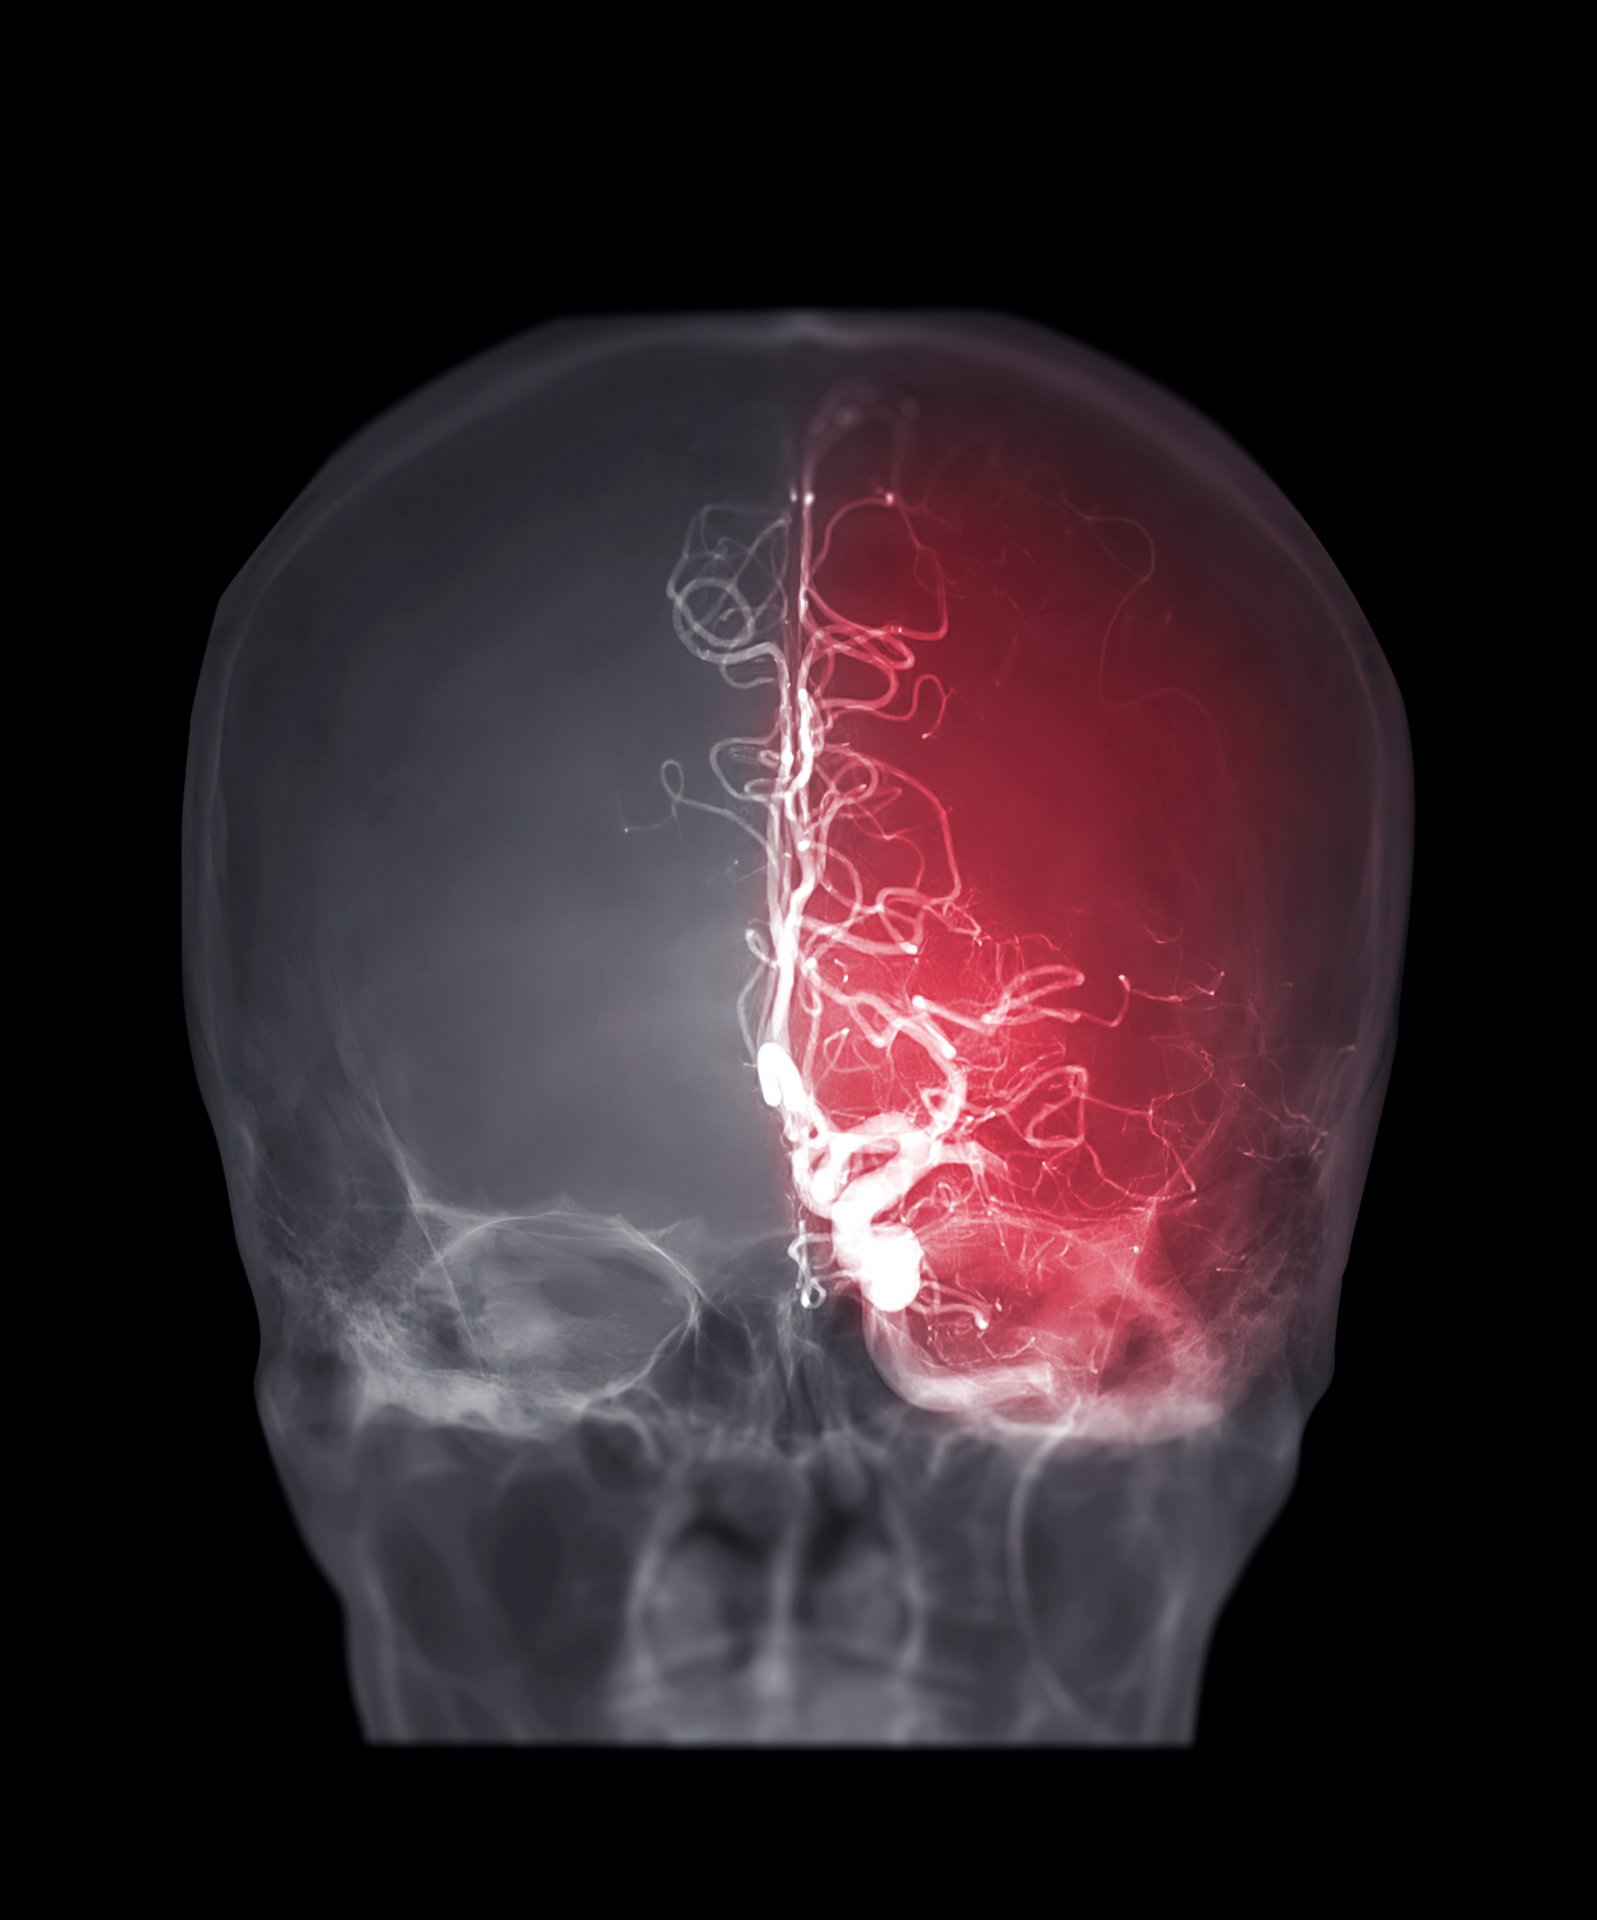

Bei neurologischen Notfällen wie Schlaganfällen oder Hirnblutungen ist eine schnelle und präzise Diagnostik entscheidend. Wir nutzen moderne Bildgebung mittels CT und MRT sowie Ultraschall für eine zielgenaue Diagnose. Am AKH-Celle halten wir alle diagnostischen und therapeutischen kathetergestützten Verfahren, vor um in der Folge - falls notwendig - umgehend eine möglichst schonende, minimal-invasive Behandlung komplexer Gefäßerkrankungen des Gehirns und Rückenmarks durchzuführen.

- Intrakranielle Aneurysmatherapien (z.B. Aneurysma-Coiling und Flow Diversion)

- Embolisationen von arteriovenösen Malformationen und arteriovenösen Fisteln (AVM/AVF)